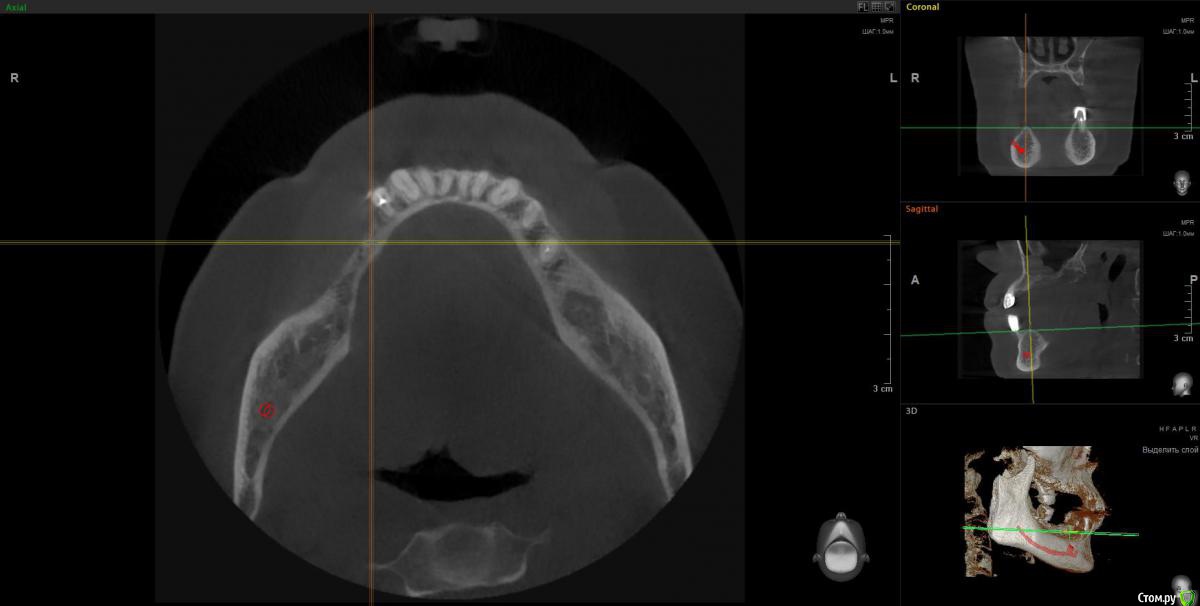

Irouil Опубликовано 10 апреля, 2018 Поделиться Опубликовано 10 апреля, 2018 1. Внизу справа можно имплантироваться, мягкотканную пластику провести нужно будет только 2. В пазухе слева живёт грибок, надо удалять независимо от вида имплантации на верхней челюсти 3. Про зигомы надо ещё КТ самих скул 4. С трефоилом знаком только по наслышке, но он используется (вроде бы) только на нижней челюсти, там необходимости его я не вижу. Коллеги, что знакомы с ним лучше, могут поправить. 1 Ссылка на комментарий

Irouil Опубликовано 10 апреля, 2018 Поделиться Опубликовано 10 апреля, 2018 Спасибо,уважаемые доктора,в пазухе слева дентин.Там пломбировочный материал, возможно искусственный дентин, грибковое тело растет на немА мягкотканная пластика проводится одновременно с установлением имплантов?ДаДля установки имплантов внизу справа сколько их нужно и должны ли они быть меньшего размера из-за атрофии костной ткани?Меньшего чем что? Чем Ваша челюсть? безусловно. В остальном, по моему мнению, установить Вам имплантаты с покрывающими необходимости размерами особых препятствий нет. Нужно два имплантата установить. А импланты внизу слева- сколько их нужно- один или два? С нетерпением жду ответа.Зависит от того, сколько и что будет наверху. 1-2 1 Ссылка на комментарий

Irouil Опубликовано 10 апреля, 2018 Поделиться Опубликовано 10 апреля, 2018 Спасибо-спасибо, а пазуху справа тоже надо чистить?Зависит от того, что справа планируется. Если в нее ради имплантации лезть - лучше уж и почистить, по моему 1 Ссылка на комментарий

Irouil Опубликовано 11 апреля, 2018 Поделиться Опубликовано 11 апреля, 2018 (изменено) Зря Вы наркоз не рассматриваете, левую пазуху без него навряд реально вылечить. Нужно КТ полностью смотреть, у меня его качать времени не было, но с большой долей вероятности надо будет через средний носовой ход идти и соустье расширять (если Вы на эндоскопию решитесь, что, безусловно, было бы оптимально), без наркоза это сделать практически невозможно. Там уже интраоперационно можно было бы решить - синусить и имплантироваться сразу или подождав полтора месяца. Если рассматривать классическую имплантацию (6-8 имплантатов на верхнюю челюсть), то синус лифты нужны с обеих сторон, но, опять таки, тут нужно КТ покрутить, может кто из коллег подскажет. Но есть варианты - все на 4 имплантатах, этот метод позволяет обойти верхнечелюстные пазухи, опять таки может кто из коллег подскажет, я им не обладаю. Что касается сроков, то это лучше со своим имплантологом обсуждать, тут зависит больше от Вашей готовности компоновать хирургические этапы. Я бы все по сторонам (правая/левая или наоборот) сделал с перерывом на 4-6 недель между ними и временными протезами, начиная с эндоскопии левой пазухи (ибо она может отложить имплантацию в этой области), но тут (опять и снова) надо полностью КТ глянуть и в рот тоже посмотреть. Изменено 11 апреля, 2018 пользователем Irouil 1 Ссылка на комментарий